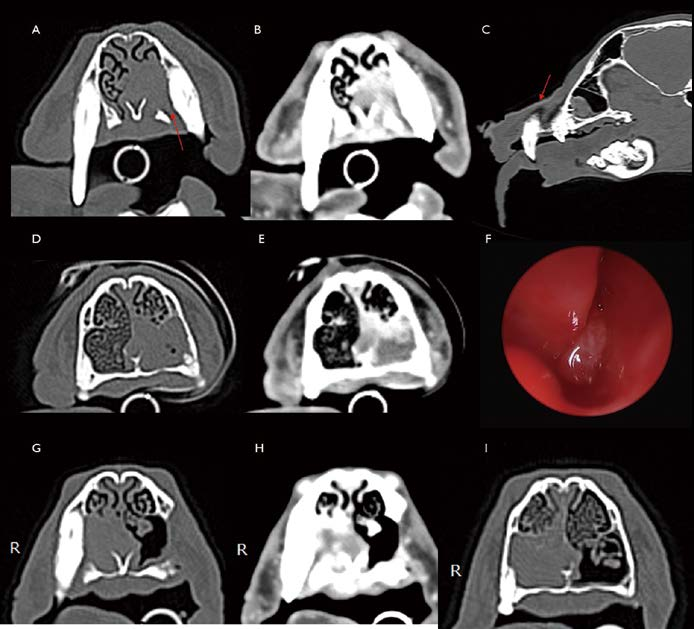

[대한수의사회지 7.png

8살 중성화 암컷 Miniature Schnauzer가 6개월 전부터 재채기, nasal discharge 증상을 보였고, 최근 왼쪽 편측으로 비출혈이 동반되었습니다. Plain X-ray에서 왼쪽 비강 내 밀도 증가 소견이 관찰됩니다(그림 7. A). CT 검사에서 왼쪽 비강 전반적으로 연조직 밀도 음영으로 채워져 있고, 일부는 nasal turbinate가 소실되어 관찰됩니다(그림 7. B, C). Nasal septum 및 large bones의 destruction은 관찰되지 않습니다. 영상학적으로 편측성이며, 일부는 nasal small bone loss를 유발한 space occupying mass 양상이므로 종양 가능성을 염두에 두고 rhinoscopy 및 여러 군데 biopsy를 실시했는데, 조직 검사는 lymphoplasmacytic to suppurative rhinitis로 확인되었습니다. 환자는 내과적 관리를 받기로 했고, sneezing 및 간헐적인 비출혈 등의 증상이 wax and wane 상태를 지속하였습니다. 전신 상태는 양호하였습니다. 그러나 1년 5개월 뒤, 왼쪽 muzzle 부위 부종, 통증 증상으로 다시 내원하였습니다. Plain X-ray에서 양쪽 비강 내 밀도가 모두 증가되어 있었고(그림 7. D), CT 검사에서 특히 왼쪽 비강 내 보다 명확해진 이질적 종괴 음영 및 이로 인한 상악골 소실 및 좌측 안구 앞쪽으로 종괴의 bulging 소견이 관찰됩니다(그림 7. E, F). 환자는 Biopsy 조직 검사에서 nasal carcinoma로 진단되었습니다. Radiation therapy 2개월 후 Plain X-ray(그림 7 G), CT 검사(그림 7. H, I)에서 오른쪽 비강 병변은 대부분 개선되었고, 왼쪽 비강 바깥으로 돌출된 부위와 왼쪽 비강 내부 일부에서도 종괴의 크기는 감소하였습니다. 환자는 비강 종양 진단 이후 방사선 치료와 보존 요법을 병행하면서 약 3년 동안 생존하였습니다.